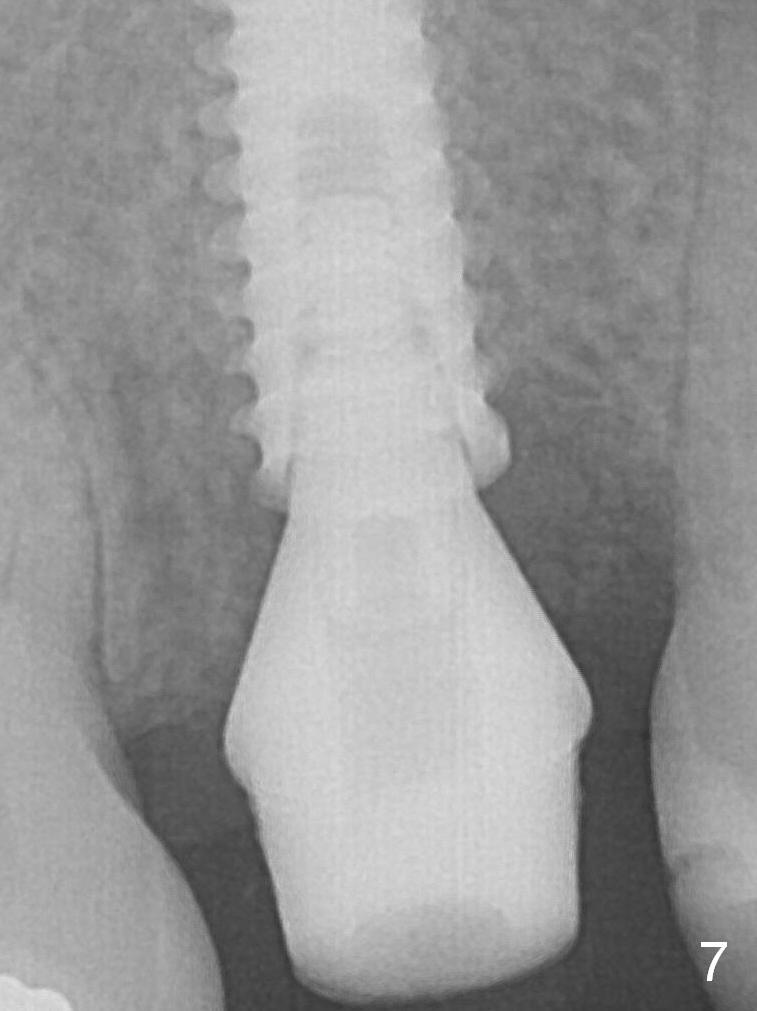

There is no bone loss 3 months postop (Fig.6,7).  The screw needs to be retightened 9 months post cementation (Fig.8).